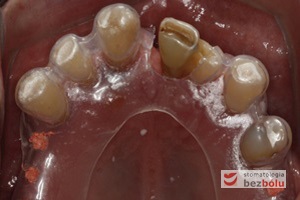

Braki zębowe w strefach bocznych szczęki i żuchwy - widoczne starcie patologiczne na skutek przeciążeń okluzyjnych w odcinku przednim

Braki zębowe w strefach bocznych szczęki i żuchwy – widoczne starcie patologiczne na skutek przeciążeń okluzyjnych w odcinku przednim

Żuchwa - widok powierzchni okluzyjnej - symetryczne braki zębowe w zakresie 4 siekaczy i trzonowców

Żuchwa – widok powierzchni okluzyjnej – symetryczne braki zębowe w zakresie 4 siekaczy i trzonowców